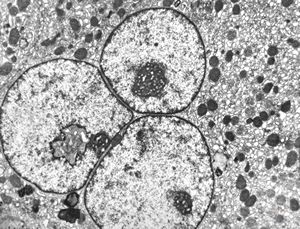

F,3m. | giant cell hepatitis - cholestasis

F,3m. | giant cell hepatitis

F,61y. | giant cell hepatitis - nuclear pseudoinclusion

F,61y. | giant cell hepatitis

F,7m. | giant cell hepatitis

F,7m. | giant cell hepatitis- intracellular cholestasis

F,7m. | giant cell hepatitis-C-collagen fibers

F,7m. | giant cell hepatitis* - dilated primary bile duct

F,7m. | giant cell hepatitis* - dilated bile duct